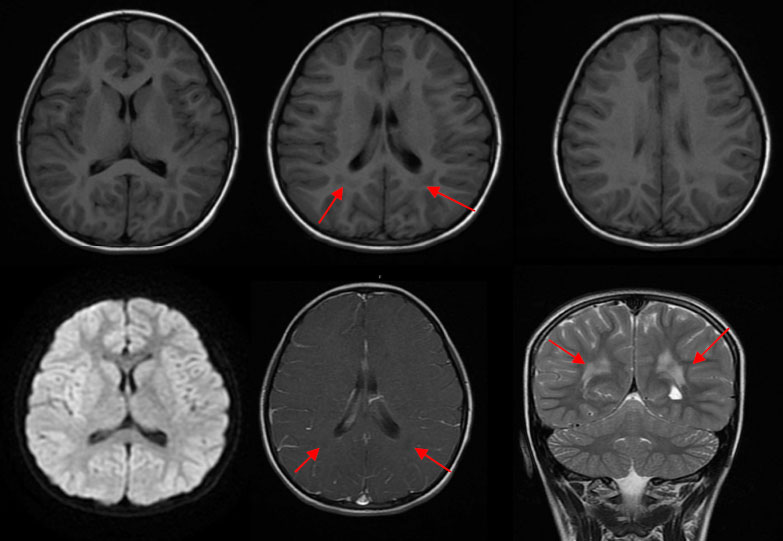

MRI表现为侧脑室旁对称性的异常信号灶,增强后可见斑点状轻度强化。

1)弥漫型:大脑半球、基底节区、丘脑及小脑半球实质内斑片状、斑点状等或长T1、长T2信号灶,周围可见水肿或无明显水肿,病变可累及灰白质。增强后呈斑片状、斑点状、脑回状轻-中度强化。

2)局灶型:单发局限性上述信号灶。